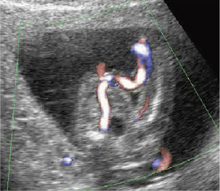

医療従事者の間で話題になっているのみならず,ママたちの書くブログにもNTの話題が載る。このことが胎児心疾患の診断時期に影響を与えた。羊水による染色体検査の実施を勧められている,あるいは自ら考えているママたちをカウンセリングするにあたって,胎児心疾患の存在,もしくは否定は重要な情報である。羊水による染色体検査は妊娠16週に実施されることが多いので,超音波による胎児臓器のスクリーニングもこれに合わせて行われることが多くなった。図5,6に示す症例は,NTが見つかり,引き続き胎児超音波精査を行ったところ,妊娠15週で両血管右室起始と診断された。染色体検査の結果はTrisomy18。

この時期の胎児心臓の観察では,経膣超音波と,経腹超音波の両方を使用するのが好ましい。ダイナミックフローのような,分解能に優れた血流表示が必須である。心臓が近くにあれば,経膣超音波の方が分解能に優れるが,胎児の左右の認識が困難なことがある。妊娠16週胎児心臓スクリーニングでの観察項目は,(1) 四腔断面,(2) 大動脈の起始部,(3) 肺動脈の起始部,(4) 両大血管の走行,(5) 大動脈アーチの追跡である。白黒画像とダイナミックフローの両方を使えば理解が得やすい。

![]() 図5 Trisomy18 この症例の頸部には多?胞なNTが観察された。 |

![]() 図6 Trisomy18 右室起始の大動脈を示す。妊娠15週の心臓スクリーニングで大動脈, 肺動脈とも右室起始(DORV)が認められた。羊水染色体検査の結果はTrisomy18と診断された。 |